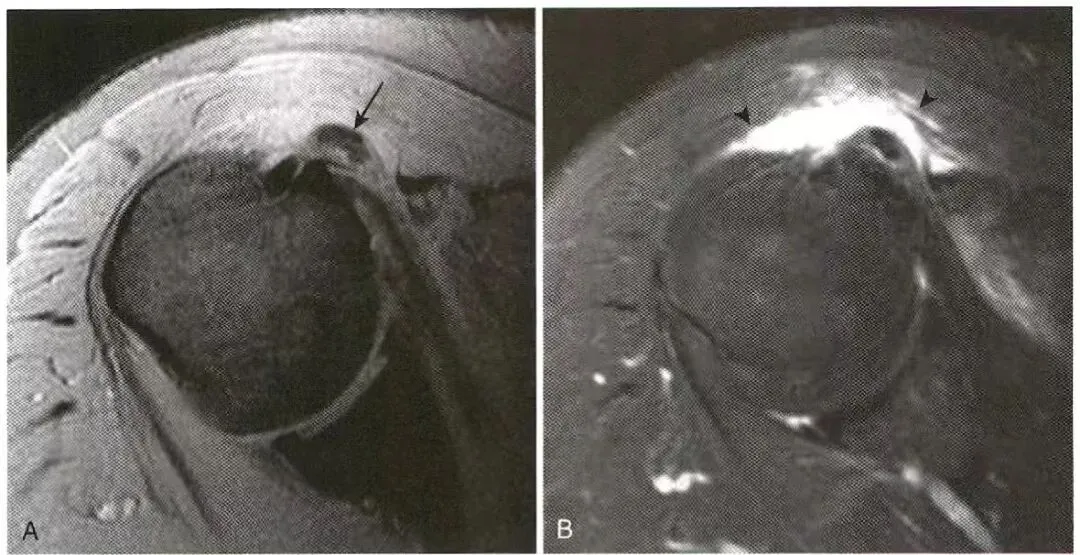

肌腱脱位:  A,肱二头肌长头腱脱位,位于部分撕裂的肩胛下肌腱内。  B,腓骨肌腱(箭号)从腓骨后(大箭头)向外侧脱位,腓骨上支持带已脱离其在腓骨上的附着处(小箭头)。